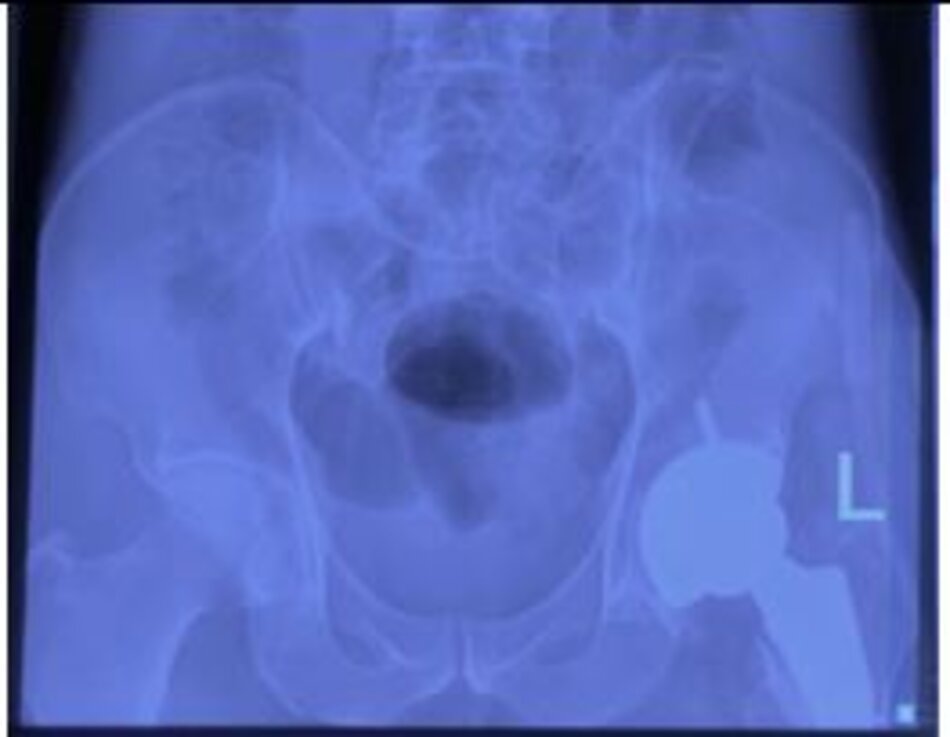

Hình ảnh vỡ xương chậu phức tạp